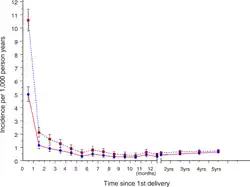

| Rates of psychoses among Swedish first-time mothers | |

PPP is rare, reported to occur in about 1 to 2 of every 1000 childbirths (0.9 to 2.6 per 1,000).[6][41] Reported cases are thought to underestimate the actual occurrence of PPP due to the probability of some individuals avoiding hospitalized care to avoid separation from their child (particularly in locations with no mother-baby units) or fear of stigma, as well as the likelihood of misdiagnosis with other postpartum disorders.[11] The first month following childbirth is associated with a higher relative risk for hospital admission due to psychosis when compared to other times in an individual's life.[42] While no specific genetic factors have been linked to PPP, a family history or personal history of bipolar disorder has been strongly associated with higher risk for PPP episodes (see Risk Factors).[6]

Psychoses triggered in the first two weeks after the birth – between the first postpartum day (or even during parturition[51]: 115–116 until about the 15th day – complicate approximately 1/1,000 pregnancies.[49] The impression is sometimes given that this is the only trigger associated with childbearing. But there is evidence of four other triggers – late postpartum,[51]: 200–204 prepartum,[51]: 190–195 post-abortion[51]: 184–190 and weaning.[51]: 204–206 Marcé, widely considered an authority on puerperal psychoses,[67] claimed that they could be divided into early and late forms; the late form begins about six weeks after childbirth, associated with the return of the menses.[68] His view is supported by the large number of cases in the literature with onset 4–13 weeks after the birth, mothers with serial 4-13 week onsets and some survey evidence.[69] The evidence for a trigger acting in pregnancy is also based on the large number of reported cases, and particularly on the frequency of mothers experiencing two or more prepartum episodes. There is evidence, especially from surveys,[70] of bipolar episodes triggered by abortion (miscarriage or termination). The evidence for a weaning trigger rests on 32 cases in the literature, of which 14 were recurrent. The relative frequency of these five triggers is given by the number of cases in the literature – just over half early postpartum onset, 20% each late postpartum and prepartum onset, and the rest post-abortion and weaning onset.